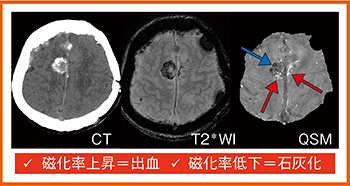

●出血と石灰化

出血と石灰化の鑑別は,臨床的に有用性が高い。髄膜腫の症例(図1)では,T2*強調画像で低信号があり石灰化と考えられるが,QSMを見ると,磁化率が低下し黒く描出される石灰化の部分(→)だけでなく,背側や反対側に磁化率が上昇して白く描出される出血(←)も伴っていることがわかる。

図1 出血と石灰化の鑑別:髄膜腫